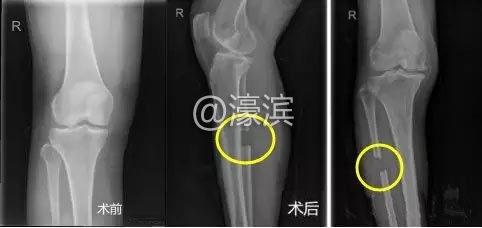

' ~% d0 h4 Y8 T% `' b  “腓骨截骨平衡术”具有手术微创、花费少、疗效好、恢复快的优点,其机理是利用生物力学理念和腓骨截除后的膝关节周围软组织的再平衡作用,达到纠正异常力线、缓解或消除疼痛的目的。作为“保膝治疗”的手段,该疗法有效避免了骨关节炎发展到晚期、不得不进行膝关节置换的痛苦。